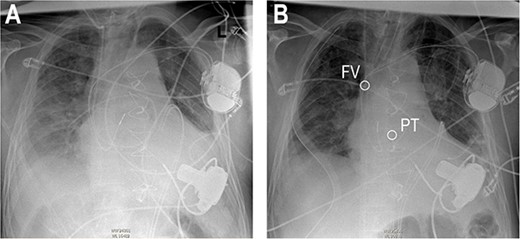

Re-sternotomy was performed. The pulmonary trunk (PT) was clamped. A 10-mm prosthetic polyester graft was anastomosed to the PT. After subxiphoid tunneling of the graft the transjugular outflow cannula was replaced by a cannula in the anastomosed graft. The cannula in the right FV remained in position in the right atrium (Figs 3 and 4). The hemodynamic situation with LVAD and RVAD flow improved immediately.

Anteroposterior thoracic radiography after LVAD implantation (A). Anteroposterior thoracic radiography after RVAD cannulation of the PT (B). Tip of cannula in the right FV, tip of cannula in the PT.